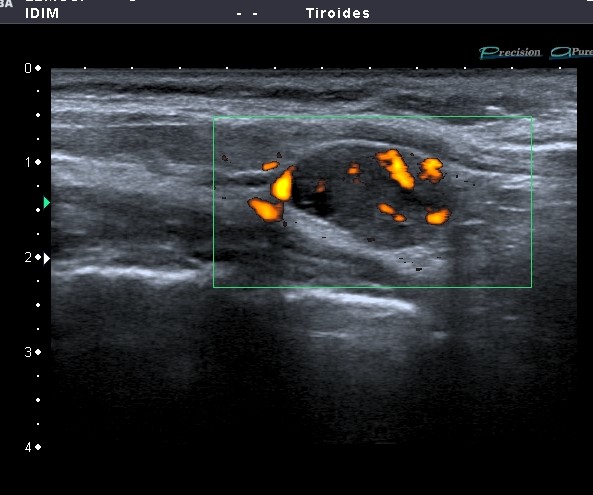

Se realizó ecografía tiroidea y partes blandas de cuello: nódulo hipoecoico de forma ovalada, aspecto sólido, con presencia de vascularización en su interior, con patrón NO hiliar. Medía 18.8mm (A) x 11.1mm (B). Se ubicaba posterior e inferior al lóbulo tiroideo derecho y presentaba límites definidos con plano de clivaje con tiroides.